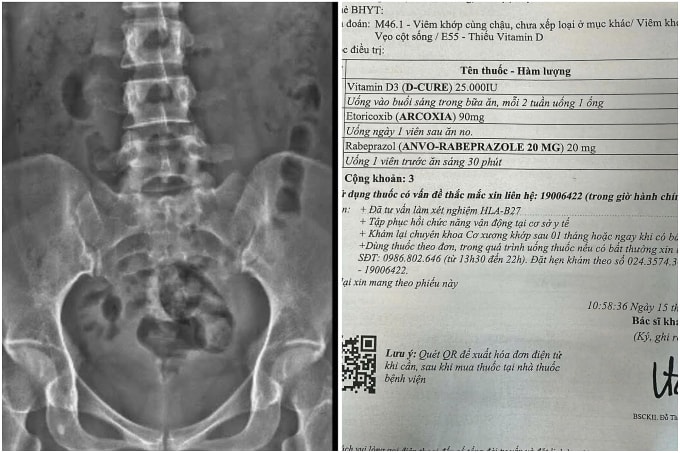

Đến khi đi ngoài ra máu, cô mới đi kiểm tra. Kết quả cho thấy viêm loét dạ dày, HP, viêm khớp vùng chậu, vẹo cột sống, thiếu vitamin D. Bác sĩ phát hiện cô bị tăng huyết áp vô căn, cần theo dõi định kỳ. Nghe vậy, Linh thở dài. "Hóa ra, mất tiền còn kiếm lại được, mất sức khỏe là mất tất".